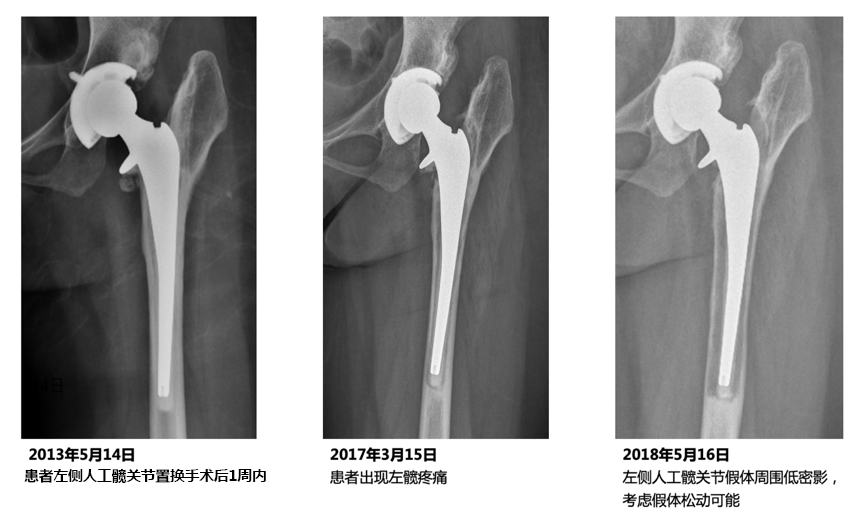

我在临床中就遇到过一位46岁乳腺癌患者。5年前接受了左髋全髋置换术,术后患者的功能恢复得非常好。但是,患者在髋关节置换术后1年发现乳腺癌并接受化疗,随后服用他莫昔芬行内分泌治疗。1年前,也就是关节置换术后的4年,乳腺癌内分泌治疗后3年,患者无明显诱因出现左侧髋部及大腿前方酸胀样疼痛,上下楼梯及长时间行走后加重,休息后可缓解。同时伴有行走受限,行走距离200米。X线检查后,我们可以明显的看到,左侧人工髋关节假体周围骨量丢失,造成人工关节假体松动。

图片 1.png一般情况下,人工髋关节的使用寿命平均在15~20年,但这位乳腺癌患者因为接受乳腺癌的内分泌治疗,导致其置换的关节寿命由20年缩短为不到4年,早期出现人工关节假体松动。